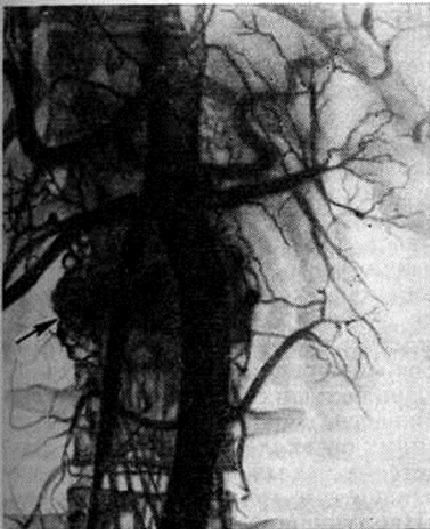

При Гемангиома кости никогда не наблюдается сплошного остеолиза или крапчатых склеротических включений, характерных для метастазов опухолей в позвоночник. При компрессионном переломе позвонка с целью дифференциальной диагностики метастаза опухоли и Гемангиома проводят ангиографию. Так, например, в результате ангиографии в теле поясничного позвонка (L3) вместо предполагавшегося метастаза опухоли была обнаружена кавернозная Гемангиома (рисунок 2).

Рис. 2. | ||